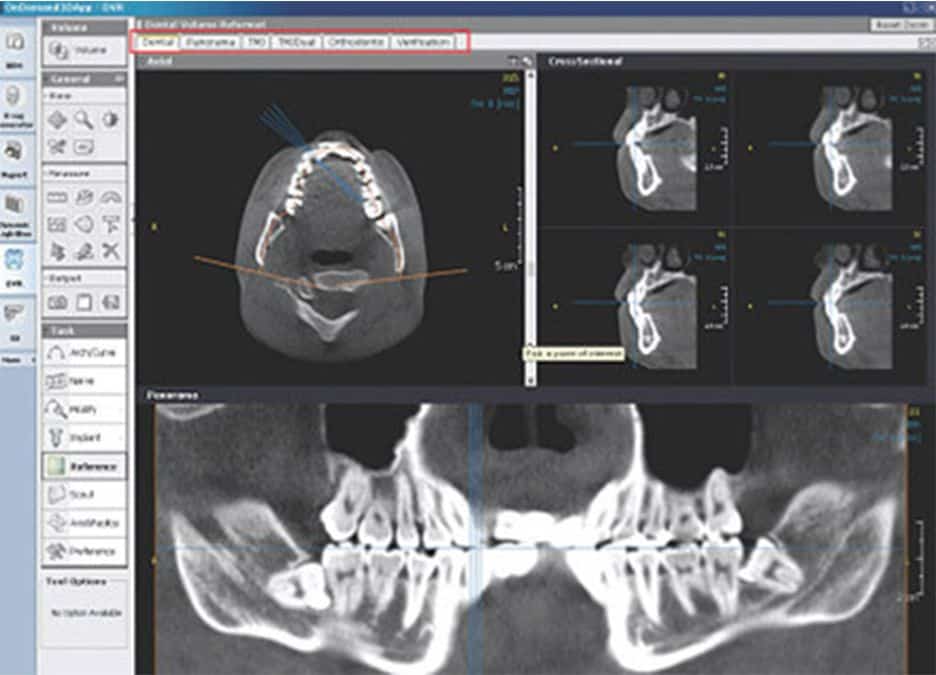

Modulul Dental prezinta o mare parte din functiile modulului DVR. Spre deosebire de modulul DVR, modulul Dental ofera si functii ale modulului 3D, precum zoom-ul 3D care permite marirea detaliilor 3D.

Functionalitati: planificare implanturi, analiza TMJ, zoom 3D, trasare nerv.